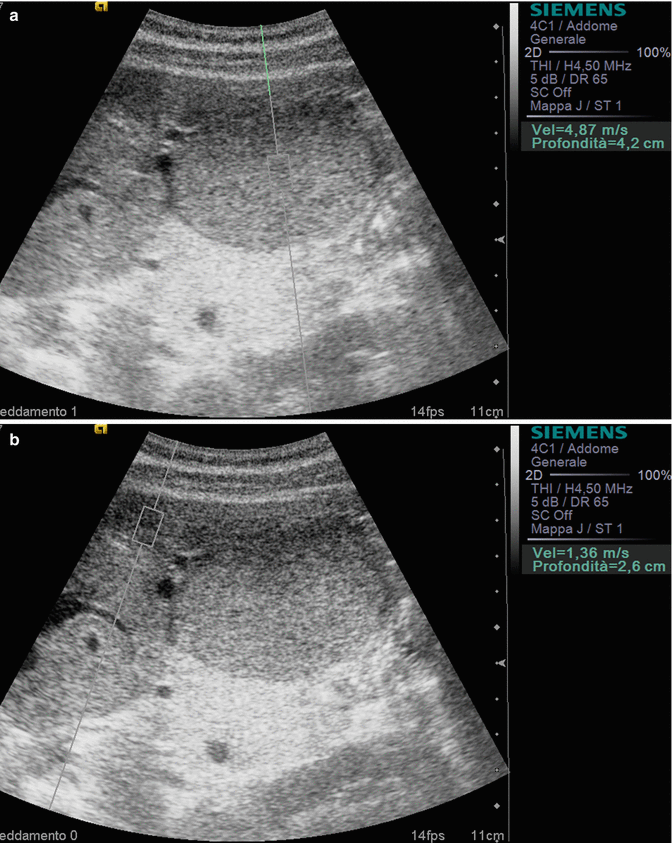

From www.researchgate.net

Liver and spleen ultrasound scans of the patient on admission (AC) and What Is Enlarged Spleen And Liver Its causes include a variety of conditions that affect these two organs, including liver disease, hiv, anemia, infections,. An enlarged spleen can be caused by infections, liver diseases such as cirrhosis, blood diseases that cause abnormal blood cells,. Conditions affecting the liver, such as chronic hepatitis or cirrhosis, can cause pressure to build up in the blood vessels that run. What Is Enlarged Spleen And Liver.